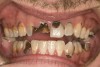

Joe soon learned how to manufacture the drug. His need for meth soon consumed his every thought. He basically lived to do more meth. He admitted that he had made some poor choices. Unfortunately once the addiction kicked in, he no longer had a choice, he had to use. This was his end result (Figure 4 through Figure 6). From these photographs, one might think that he had used the drugs his entire life; however, this progression happened over the course of only about 1 year of smoking the drug. Because of the caustic chemicals (muriatic acid, hydrochloric acid, lithium, etc) his teeth started to blacken, then break.

When Joe was finally arrested, his teeth were in the state seen in Figure 4 through Figure 6. He entered rehab, then served his time in prison. He received no dental treatment in prison. Once he was released on probation, he found it quite difficult to find a job. He was hired as a mechanic but only allowed to work in the garage. He was to have no contact with the customers because his appearance was hideous. His self-esteem was at the lowest point it could be. He felt better in prison. At least there, his prison mates understood why his teeth looked the way they did; many people in prison are there as a result of a chemical dependency issue.

As a new patient, Joe was instantly likable. He had a great sense of humor. He regretted how his life had turned out. When he finally presented to this author’s practice he was 24 years old. He wanted to remove the evidence of his addiction that were visible to anyone that came in contact with him. His teeth were totally destroyed by his drug use. There was no hope of saving any of them. There were horrible infections in his jaw bones that were spreading through his system. His only option was to remove all of his teeth and have dentures made. Impressions were taken with alginate. A bite was established in maximum intercuspation. We decided that his preoperative incisal edge positions of teeth Nos. 9 and 10 were adequate to recreate the incisal edge position in full dentures.

Figure 4  PRESENTATION CONDITION By the time Joe presented for treatment after serving time in prison and going to rehab, his teeth were completely destroyed by rampant decay. Although some teeth could have been saved, the patient chose to have all of the remaining teeth extracted in order to receive a set of full dentures.

Figure 4

Figure 5  PRESENTATION CONDITION By the time Joe presented for treatment after serving time in prison and going to rehab, his teeth were completely destroyed by rampant decay. Although some teeth could have been saved, the patient chose to have all of the remaining teeth extracted in order to receive a set of full dentures.

Figure 5

Figure 6  PRESENTATION CONDITION By the time Joe presented for treatment after serving time in prison and going to rehab, his teeth were completely destroyed by rampant decay. Although some teeth could have been saved, the patient chose to have all of the remaining teeth extracted in order to receive a set of full dentures.

Figure 6